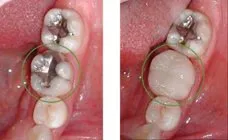

case-studies Case #6 An old Amalgam filling was replaced with a Ceramic crown (Cerec). It took only 1 hour to finish. Cerec crowns are beautiful and strong.They are 100% natural material.February 23, 2024/by Rich https://sunnyvaledentalspecialty.com/wp-content/uploads/2018/08/image1-1.jpg 240 328 Rich https://sunnyvaledentalspecialty.com/wp-content/uploads/2017/03/logo.png Rich2024-02-23 12:35:502024-05-02 11:10:09Case #6